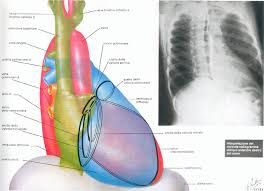

E' esperto in disturbi del ritmo cardiaco quali le bradicardie, dovute a blocchi atrioventricolari o a disfunzioni del nodo seno-atriale, la fibrillazione ed il flutter atriale, le tachicardie sopraventricolari, le aritmie ventricolari quali extrasistolie o tachicardie ventricolari congenite ed acquisite. Inoltre si occupa di impianto e programmazione di device cardiaci quali pacemaker, defibrillatori, defibrillatori biventricolari automatici (ICD – BIV) e loop recorder (dispostivi per il monitoraggio cardiaco a lungo termine impiantabili) e delle ablazioni transcatatere delle aritmie.